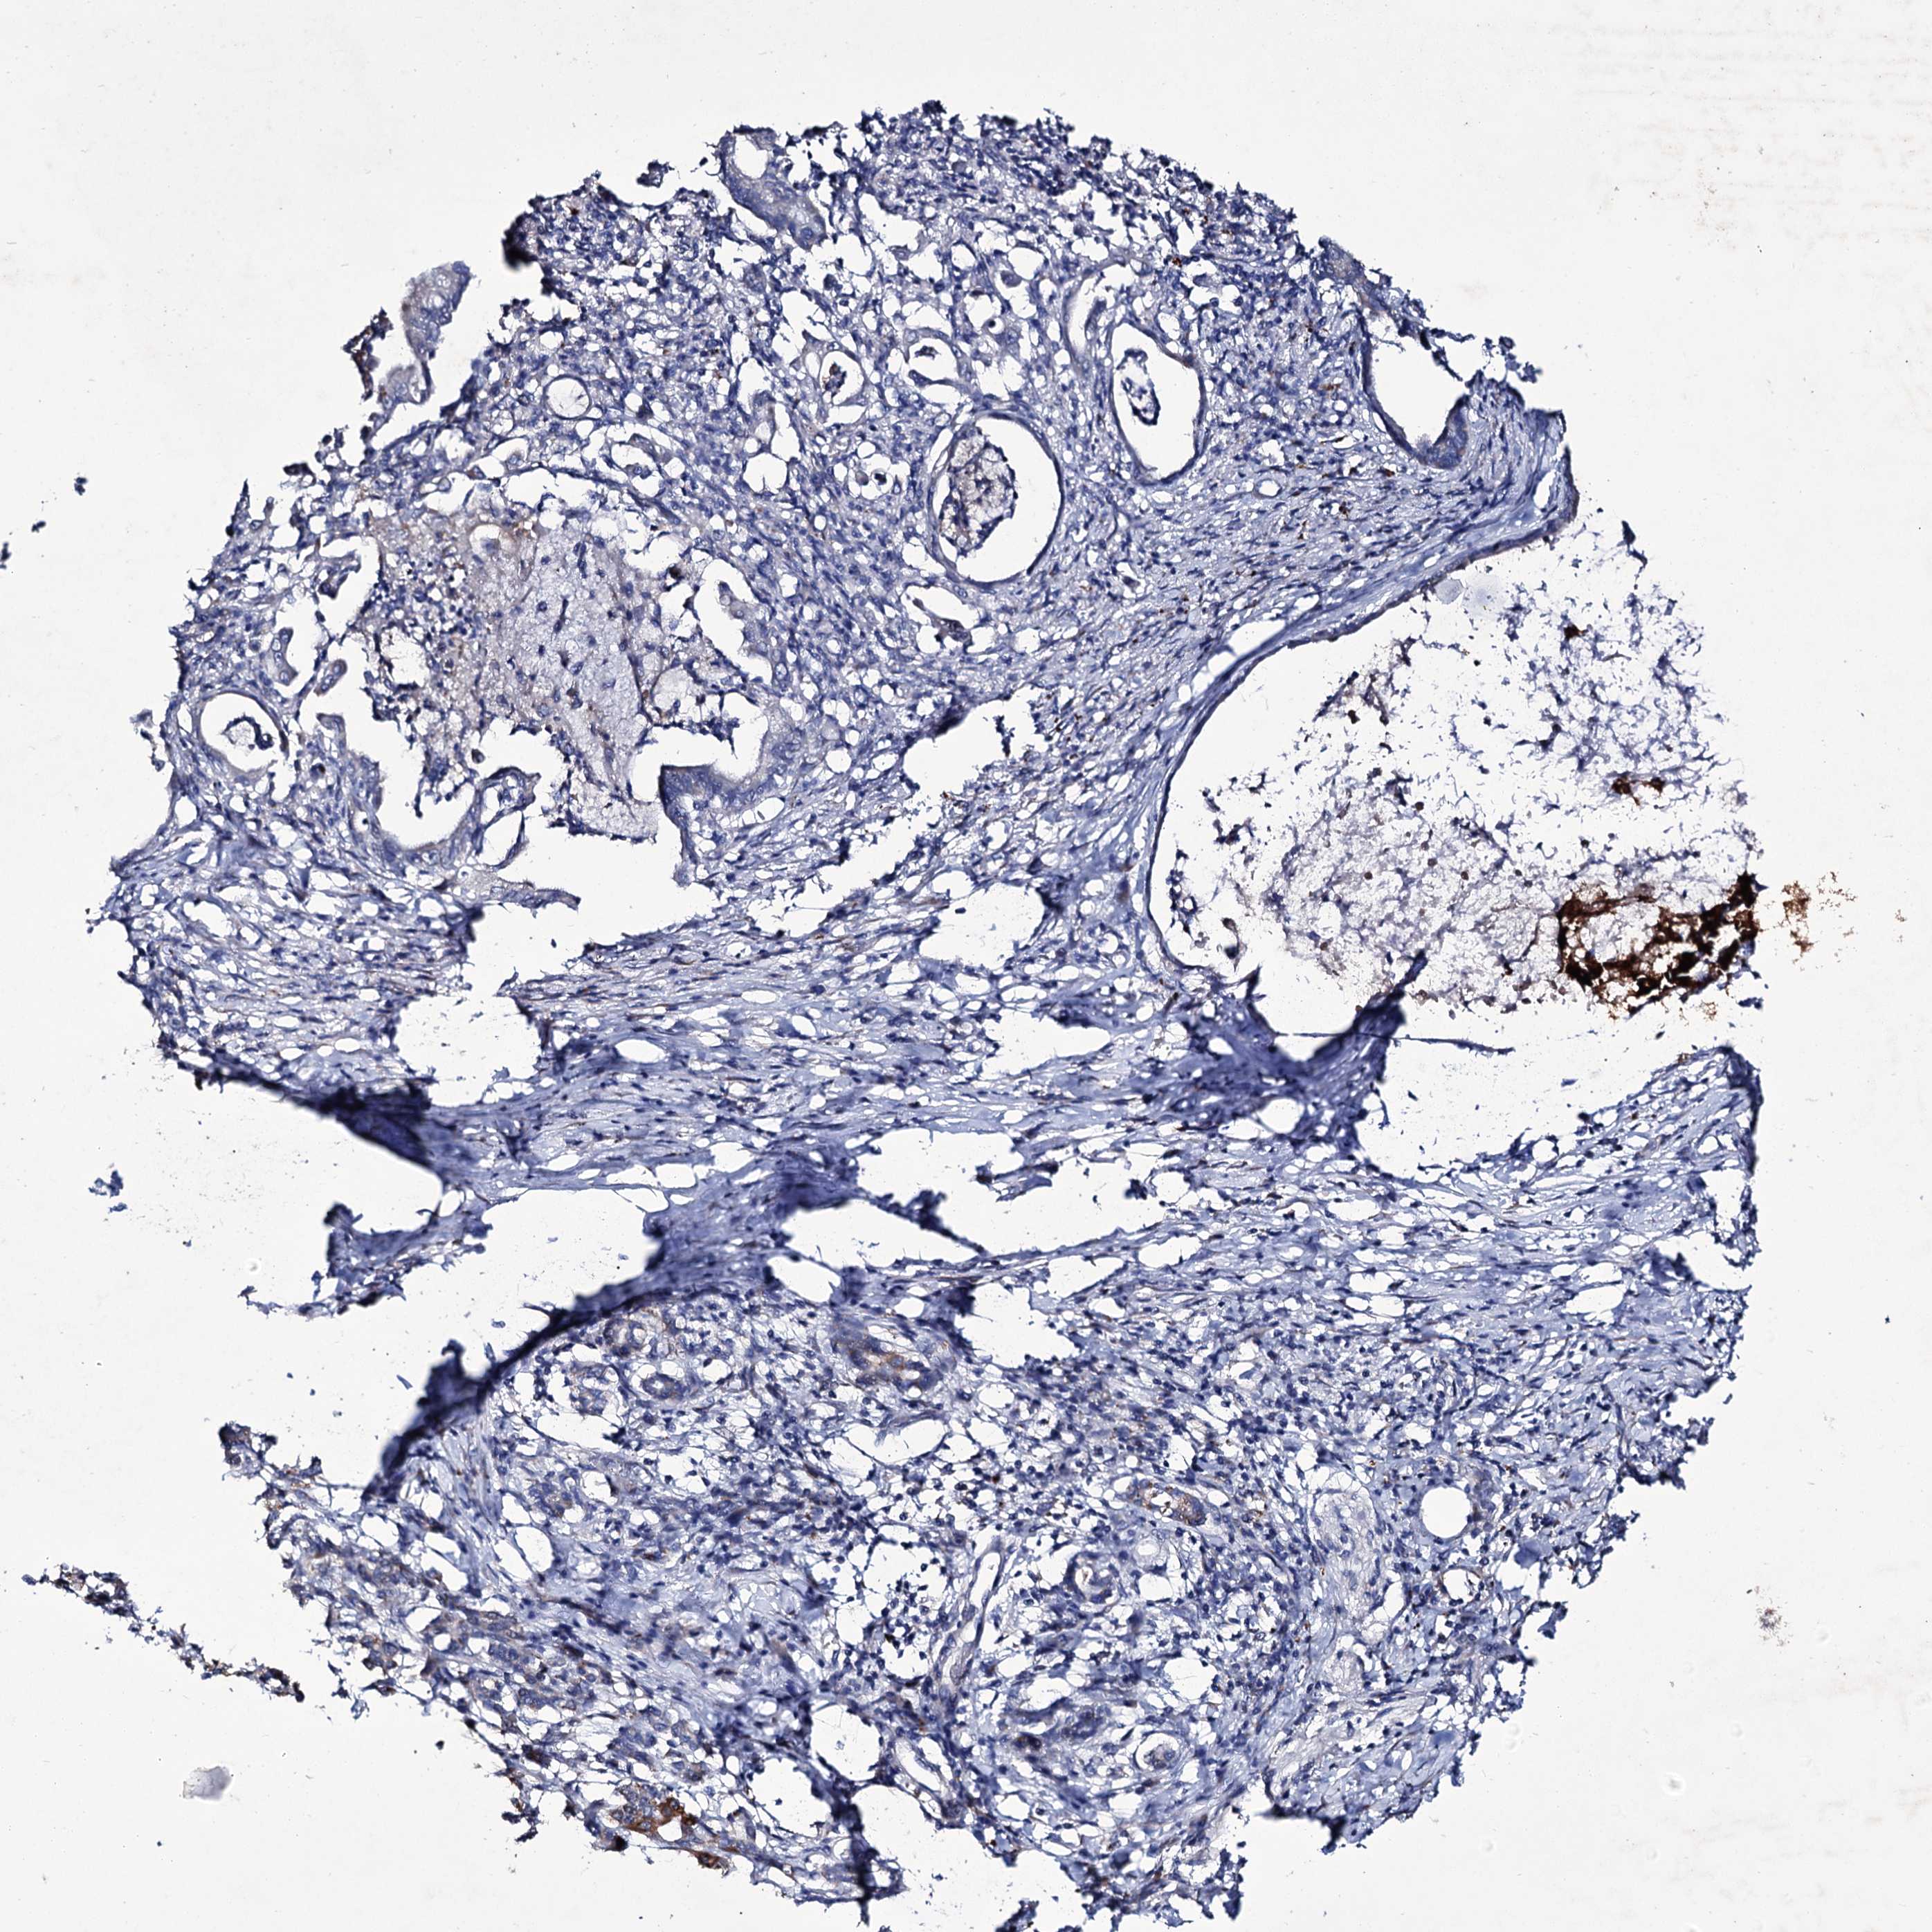

PANCREATIC CANCER - Protein expressioni

A mouse-over function shows sample information and annotation data. Click on an image to view it in a full screen mode. Samples can be filtered based on level of antibody staining by selecting one or several of the following categories: high, medium, low and not detected. The assay and annotation is described here.

Note that samples used for immunohistochemistry by the Human Protein Atlas do not correspond to samples in the TCGA dataset.

Antibody stainingi

Antibody staining in the annotated cell types in the current human tissue is reported as not detected, low, medium, or high, based on conventional immunohistochemistry profiling in selected tissues. This score is based on the combination of the staining intensity and fraction of stained cells.

Each image is clickable and will lead to virtual microscopy that enables deeper exploration of all samples and also displays staining intensity scores, fraction scores and subcellular localization as well as patient and tissue information for each sample.

Antibody HPA039366

Staining

High

Medium

Low

Not detected

Intensity

Strong

Moderate

Weak

Negative

Quantity

>75%

75%-25%

<25%

None

Location

Nuclear

Cytoplasmic/membranous

Cytoplasmic/membranous,nuclear

Adenocarcinoma, NOS